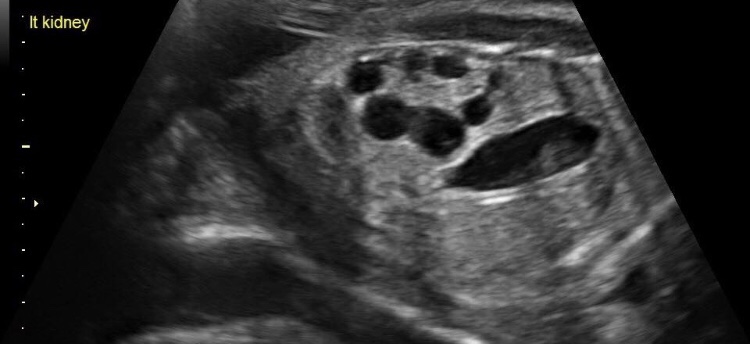

MCDK can be found as early as twenty-three weeks via ultrasound. Yes,it can be genetic, but it is very rare that the baby has inherited from his/her family member(s). This condition has nothing to do with anything mom did or didn’t do. Lack of development in the kidneys is unpreventable.